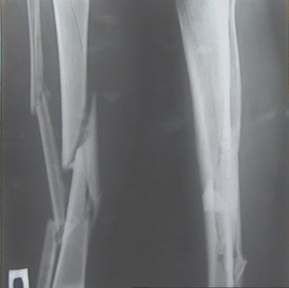

Уважаемые коллеги! На консультации больной предъявляет жалобы на хромоту (укорочение - 2см), боль в месте перелома при нагрузке (спортсмен).

Семь месяцев назад получил закрытый перелом, лечился консервативно в одной из больниц города. Как-бы кто лечил? Сам склоняюсь к LCP с костной пластикой.

Юрий Алексеевич, привет. А перелом то вроде сросся! -правда с варусом - угол можно посчитать у Вас по снимкам (в письме - суставов нет в прямой проекции). Я бы не спешил, с открытой хирургией тем более. Риски велики. Укорочение абсолютное тоже мизерно. А коррекцию оси сделал бы попозже малоинвазивным методом по Илизарову ГА.